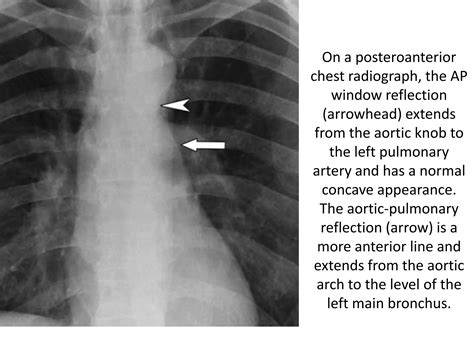

• Chest X-ray: This is often the first diagnostic test performed. It can show the position of the mediastinum and any abnormalities in the lungs or pleural space.

• mediastinal shift x ray

• mediastinal shift in pneumothorax